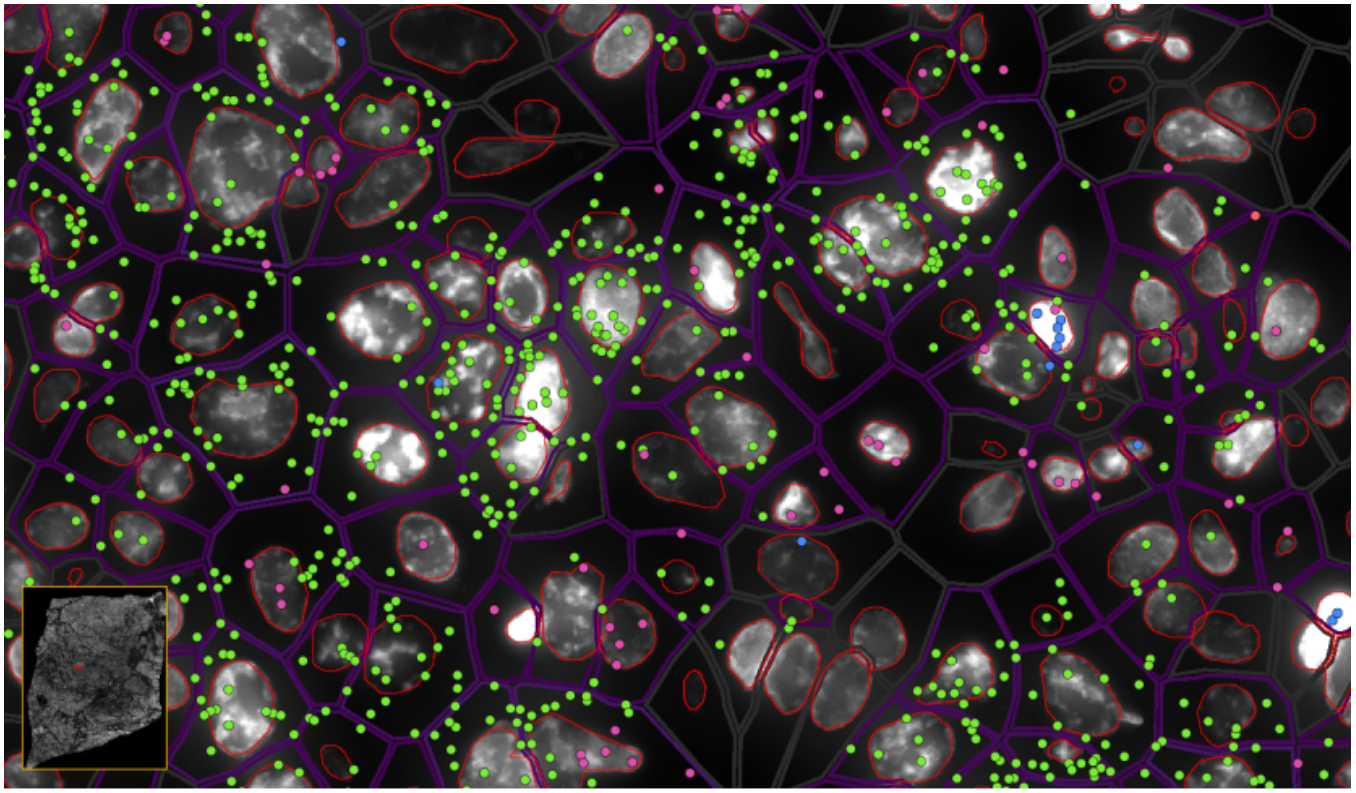

ͼ6-1£ºÊµÏÖµ¥Ï¸°û/ÑÇϸ°û·Ö±æÂʵĿռäת¼×é·ÖÎö£¬Â̵ã-EPCAM , À¶µã-KLRD1 £¬·Ûºìµã-LILRB2

ͼ6-2£ºÊµÏÖµ¥Ï¸°û/ÑÇϸ°û·Ö±æÂʵĿռäת¼×é·ÖÎö£¬Â̵ã-EPCAMת¼±¾